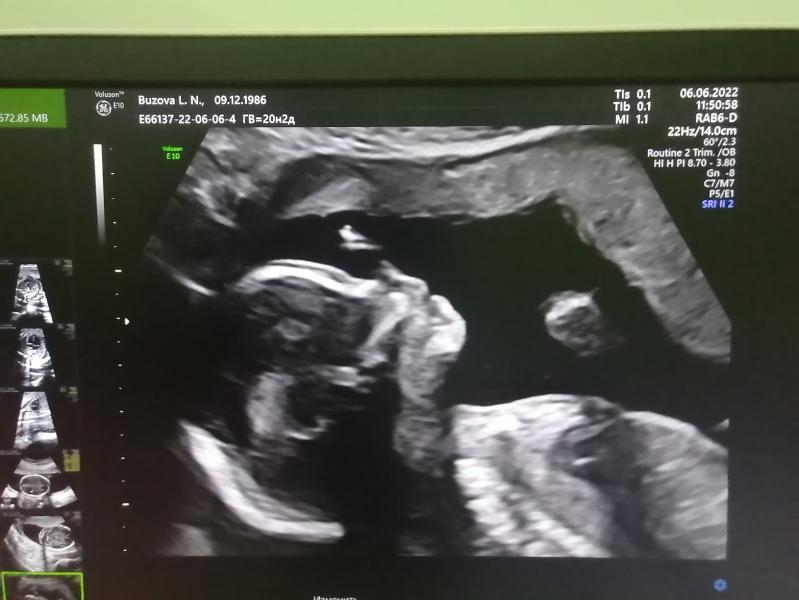

Доброе утро, девочки. 🤗 малышке нашли специалиста грамотного действительно подтвердила, что нашей доченьки "Зеркальное сердце- декстрокардия "😒 расположено в правую сторону и вены которые впадают в серце нормального человека вены нижяя и верняя расположены правильно право лево, а моей малышки на оборот. . Может, кто сталкивался с таким? Врач сказала это очень редкий случай. При этом она не пугала, но сказала, что наблюдаться 3 триместре повторить Эхо узи сердца плода , чтобы ничего больше не выл...